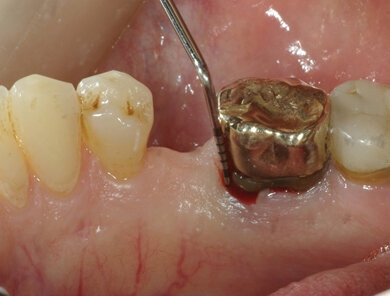

Dopo avere estratto atraumaticamente il molare compromesso, si è proceduto alla pulizia dell’alveolo, mediante curettaggio e irrigazione di soluzione salina sterile. Il periostio è stato distaccato dall’osso alveolare attorno al margine gengivale e, con una minima incisione di rilascio, sono stati parzialmente sollevati due lembi di ridotte dimensioni – linguale e vestibolare – in modo da facilitare le operazioni successive. Il sito è stato dunque innestato con il sostituto osseo granulare, idratato con fisiologica sterile e successivamente protetto con la membrana in pericardio, posizionata a doppio strato. I margini alveolari e la membrana sono stati quindi stabilizzati con un singolo punto incrociato eseguito con sutura non riassorbibile. La membrana è stata quindi lasciata esposta all’ambiente orale e la gengiva lasciata guarire per seconda intenzione. L’innesto osseo utilizzato (Osteoxenon, OX-35, Bioteck, Vicenza) è in forma granulare (dimensione granuli 0,5-1 mm), ed è composto da una miscela cortico-spongiosa in proporzione 1:1. Tale innesto è ottenuto applicando al tessuto equino di origine un processo di eliminazione enzimatica degli antigeni. Poiché il processo è effettuato a temperature mai superiori ai 60°C e non prevede l’uso di collagenasi, è in grado di mantenere il collagene osseo all’interno del biomateriale, caratteristica che può favorire la formazione di nuovo tessuto osseo. La membrana utilizzata (Heart, HRT-001, Bioteck, Vicenza) è un foglio omogeneo di pericardio equino, di dimensioni 25x25 mm. Anche in questo caso, gli antigeni sono stati eliminati selettivamente mediante un processo non aggressivo con specifici enzimi. Tanto l’innesto quanto la membrana sono stati sterilizzati mediante irraggiamento con raggi beta a 25 kGy.

La rimozione delle suture è avvenuta a 7 giorni dall’intervento. Il paziente è stato controllato dopo ulteriori 21 giorni e ogni mese per i successivi 12 mesi (Fig. 3). Successivamente è stato richiamato per i controlli ogni 6 mesi. Il paziente non ha sofferto di alcuna complicanza post-operatoria. La guarigione completa della gengiva per seconda intenzione è avvenuta nell’arco dei 60 giorni successivi all’intervento. Sia ai controlli intermedi che al controllo a 24 mesi non si è osservata perdita del volume alveolare, né in senso verticale né in senso orizzontale (Figg. 4, 5).

Fig. 3 - a: l’alveolo post-estrattivo prima dell’applicazione della tecnica di ridge preservation. b: l’alveolo viene riempito con il sostituto osseo equino e protetto con una membrana in pericardio in doppio strato, lasciata esposta. c: aspetto clinico a 7 giorni. Il processo di guarigione della mucosa è in corso e non si rilevano segni di infiammazione o infezione. d: a 21 giorni si osserva la presenza di tessuto di granulazione e la guarigione è in fase avanzata.